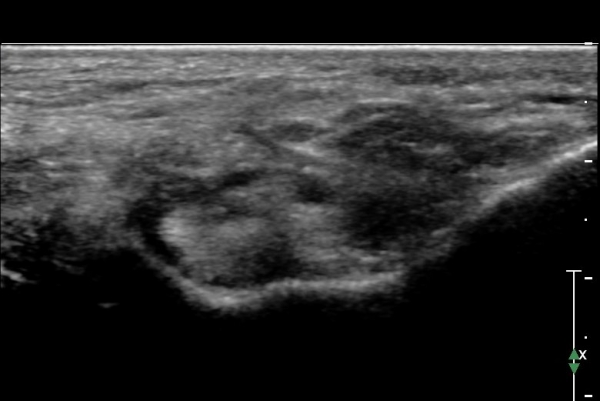

Å½ÃËÁö¸¦ Á¶±Ý ´õ ¸»´ÜÀ¸·Î À̵¿ÇÏ¿© naviculocuneiform °üÀý À§Ä¡¿¡ ¿À´Ï Knot  of  Henly °¡ °üÂûµÇ°í

À幫Áö±¼±Ù°Ç ³»ÃàÀ¸·Î  ¼ö¾×Àú·ù°¡ °üÂûµÇ°í ³»Ãø Á·Àú½Å°æÀº Ç¥ÃþÀ¸·Î  ÀüÀ§µÇ¾î º¸ÀÓ(»çÁø 4).